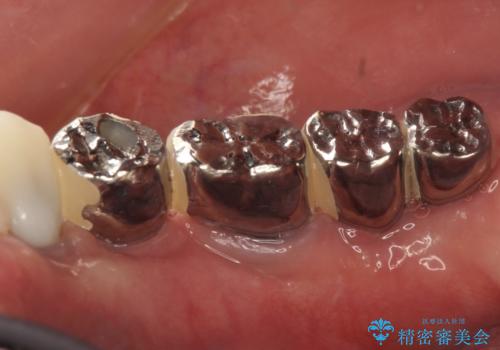

虫歯だらけ、歯周病 崩壊した口腔の再建 フルマウスリコンストラクション

かみ合わせの力が非常に強く、夜間の歯ぎしり・食いしばりもひどかったため、奥歯はメタルオクルーザルの設計でかぶせ物を製作しています。

かぶせ物の種類:PFZ / PFM metal occlusal